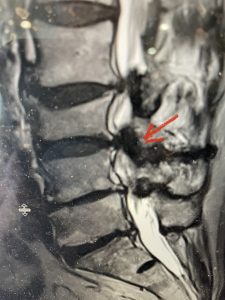

This 66 year-old male with Factor XI deficiency had originally had a decompressive laminectomy L2-S1 and in situ fusion about three years prior for severe thecal sac compression mainly due to severe epidural lipomatosis (Fig 4).

(Fig 4a) Sagittal (a) and Axial (b) T2-weighted lumbar MRI demonstrating severe spinal stenosis L2-5 (arrow)and extruded disc at L3-4 on axial image (arrow)

Epidural lipomatosis is a relatively rare condition where normally present fat in the epidural space is hypertrophied and can cause severe thecal sac compression. It is generally deposited more in the lateral and dorsal epidural space. This can be caused by long term steroid use and obesity, but also can be idiopathic. He had done well until more recently had developed low back pain with bilateral thigh pain and numbness. He had difficulty walking because of the pain. A new MRI (Fig 5) revealed that he had developed severe degeneration of the L1-2 segment above his prior decompression and fusion with a large extruded disc/osteophyte, right greater than left with severe thecal sac compression. He also had some residual T12-L3 residual epidural lipomatosis.

He had failed conservative treatment consisting of neurontin, physical therapy and epidural injections. He underwent revision laminectomy T12-L3 to decompress and explore prior fusion. He did have significant epidural fat encountered particularly at L1-2. The fat in epidural lipomatosis has a much more firm, globular texture. It takes a while to search within the fat, gently dissecting with a Penfield 4, to finally find the thecal sac! We encountered a large subligamentous extruded fragment lateral to the thecal sac on the right above the take off of the L2 nerve root. We removed any more residual fat at the L2-3 level and T12-L1 and decompressed the sac well. On exploration of the prior fusion it was fairly solid, but had some gaps at L2-3 fusion mass. Therefore we added a T12-L3 in situ fusion to augment those gaps and because we were at the thoracolumbar junction we extended fusion to T12. Post operatively he had relief of his leg pain.